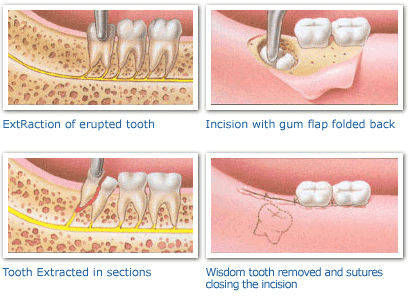

The extraction of teeth, whether simple or a complex bony impaction, is a surgical operation involving the teeth, bone, and soft tissues of the oral cavity.

Treatment of impacted wisdom teeth involves their removal using special surgical techniques and instruments appropriate for each individual case. Dr. Smith is a dentist who has specialized training in the removal of wisdom teeth and is a Board Certified Oral and Maxillofacial Surgeon. With modern anesthesia technology, it is now possible to perform these procedures in the dental office safely while you sleep, so there is little or no discomfort to you. Most teeth can be removed in an office setting, painlessly and with a short recovery period.